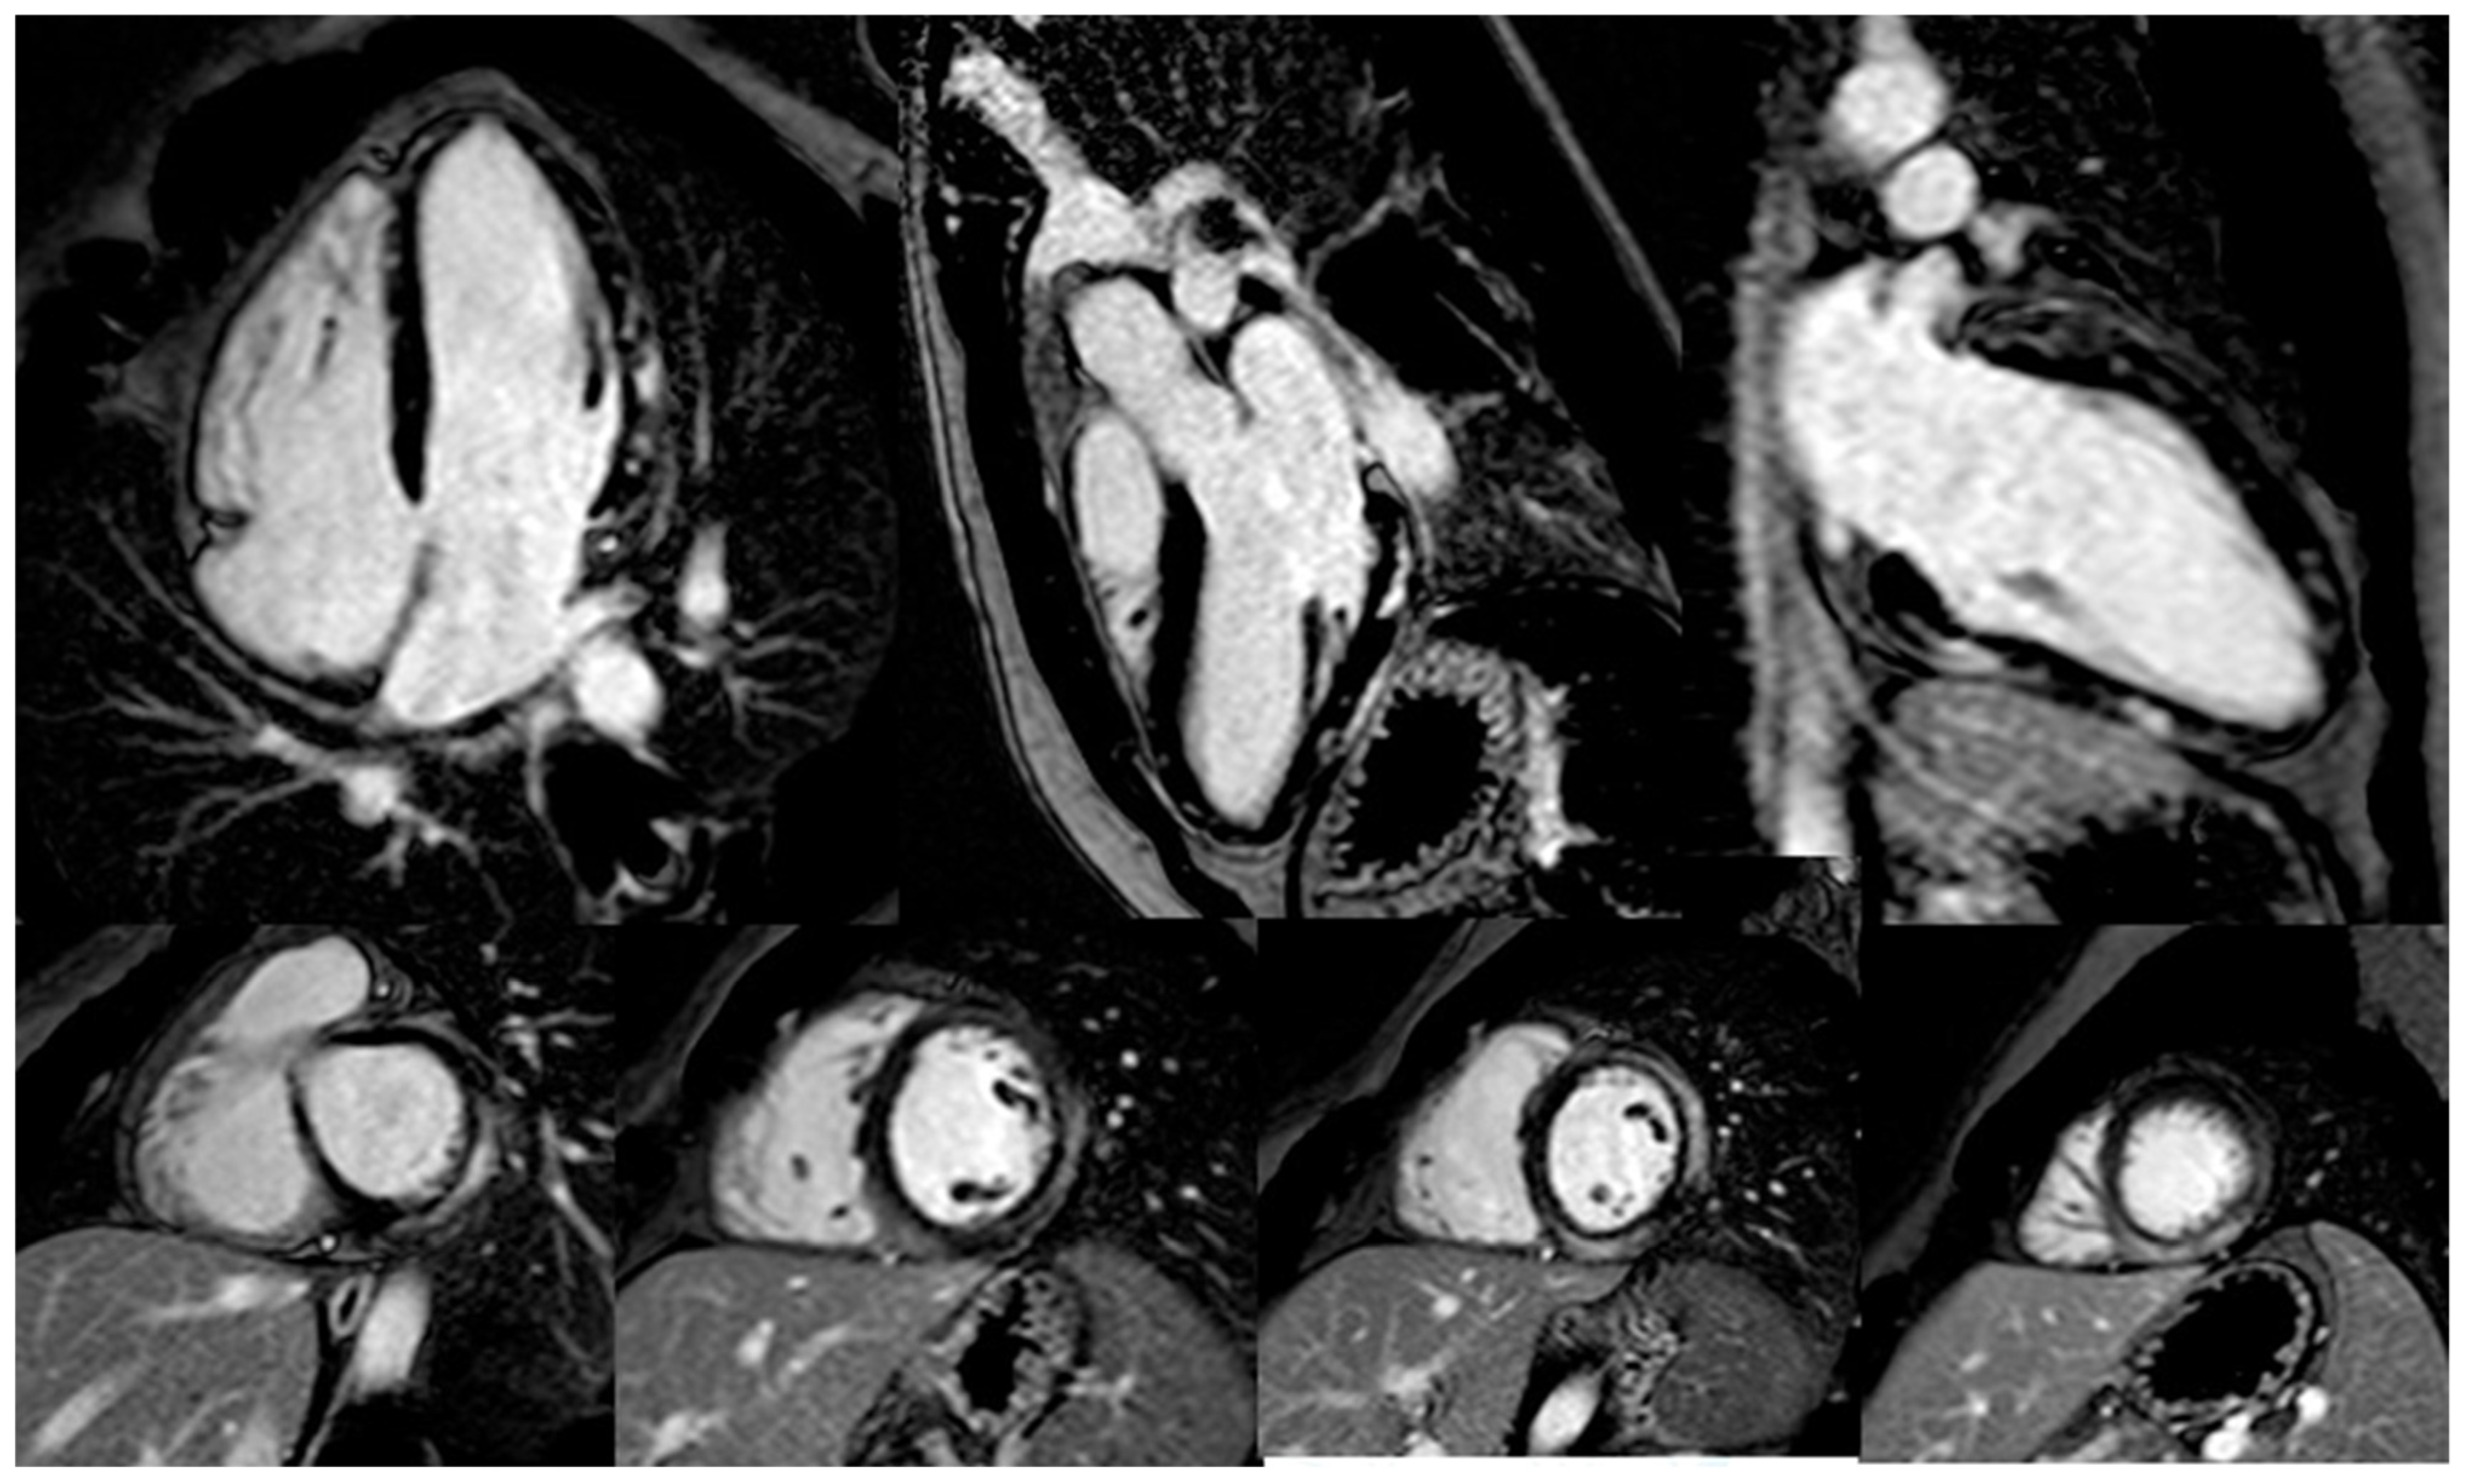

- Zhang, L.; Awadalla, M.; Mahmood, S.S.; Nohria, A.; Hassan, M.Z.O.; Thuny, F.; Zlotoff, D.A.; Murphy, S.P.; Stone, J.R.; Golden, D.L.A.; et al. Cardiovascular magnetic resonance in immune checkpoint inhibitor-associated myocarditis. Eur. Heart J. 2020, 41, 1733–1743. [Google Scholar] [CrossRef] [PubMed]

- Cadour, F.; Cautela, J.; Rapacchi, S.; Varoquaux, A.; Habert, P.; Arnaud, F.; Jacquier, A.; Meilhac, A.; Paganelli, F.; Lalevee, N.; et al. Cardiac MRI Features and Prognostic Value in Immune Checkpoint Inhibitor-induced Myocarditis. Radiology 2022, 303, 512–521. [Google Scholar] [CrossRef]